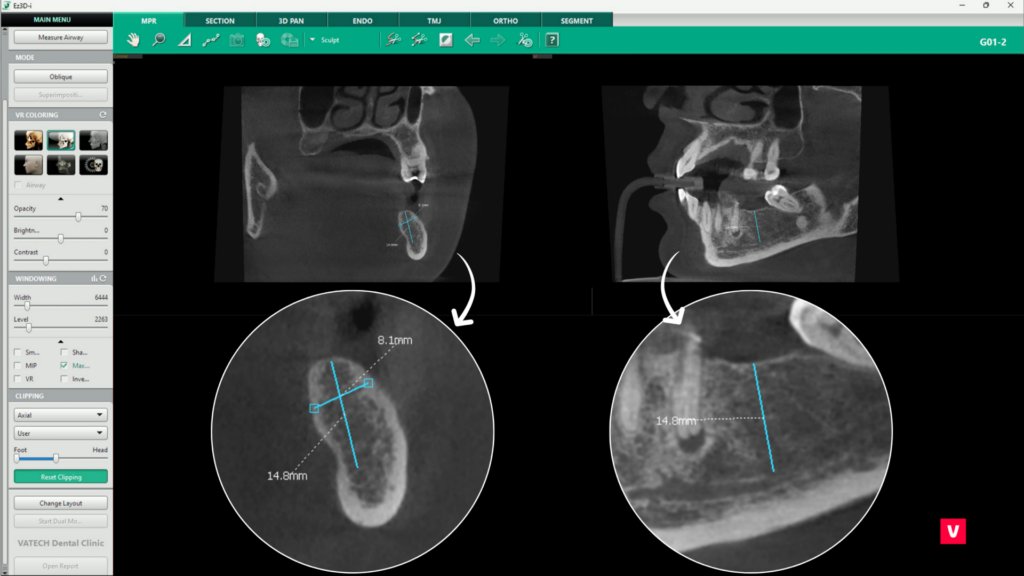

b. Densitatea osoasă a implantului

O evaluare corectă a densității osoase este esențială pentru succesul unui implant dentar. Deși am discutat în acest articolul despre numeroasele instrumentele dedicate analizării densității osoase, acest instrument specific oferă o verificare finală a compatibilității implantului cu osul în care urmează să fie plasat.

Disponibil în tab-ul 3D Pan, instrumentul poate fi activat prin selectarea opțiunii „Change Layout” din colțul stâng inferior al ecranului și alegerea unei configurații care include fereastra „Implant Bone Density”.

După selectarea implantului dorit printr-un click stânga, software-ul va genera automat un model grafic al acestuia, suprapus cu o reprezentare coloristică a densității osoase, conform scalei D1 – D5. Această reprezentare vizuală permite medicului să evalueze în detaliu structura osoasă din jurul implantului, identificând eventualele zone cu densitate scăzută care ar putea necesita proceduri suplimentare, cum ar fi augmentarea osoasă. Modelul poate fi rotit și analizat din orice unghi, oferind o perspectivă completă asupra viabilității implantului.